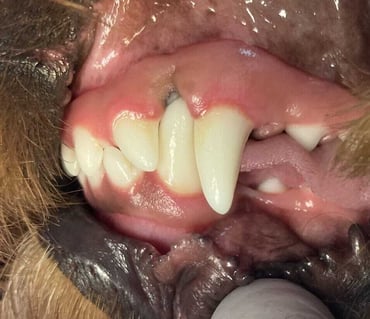

Planned crown reduction to prevent contact of a tooth crown with soft tissue usually requires the removal of a significant part of the tooth crown and it is usually impossible to avoid exposing the pulp. During vital pulp treatment, an attempt is made to maintain pulp vitality and secure further dentine production in especially immature teeth. After crown amputation, a partial pulpectomy is performed to remove approximately a further 6mm of the coronal part of the remaining pulp. This creates the space for a dressing layer, as well as further layers of glass ionomer and composite materials, to seal the coronal access site ( Figure 4).

For crown reduction of mature teeth, total pulpectomy with root canal treatment can be considered because the long-term prognosis is better than vital pulp treatment. Root canal treatment also requires less frequent radiographic monitoring than vital pulp therapy. These are advanced procedures and these cases should usually be referred.

In cats, odontoplasty of impinging maxillary third and fourth premolars can be attempted. Radiography does provide an indication of the position and size of the pulp chamber, and by careful removal of a few millimetres of the crown, contact of the remaining tooth crowns with soft tissue can be eliminated.

Dentine exposed in this way should always be sealed with unfilled resin and if the operator is not confident in the use of the material, equipment and technique, odontoplasty should not be attempted and referral or alternative treatment options considered. Radiographic follow-up is very import to confirm pulp vitality and without a firm commitment from the owners to comply with this advice, it might be better to consider extraction of the teeth causing the impingement ( Figure 5).